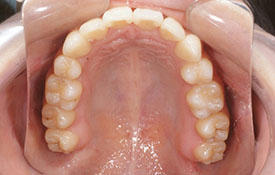

インビザラインの治療例:CASE-1

| プロフィール | 42歳 女性 |

| 所見 | 他院で行われた矯正歯科治療後の後戻りに悩まれて来院されました。 アイライナーの装着は、1日平均20時間ほどでした。 |